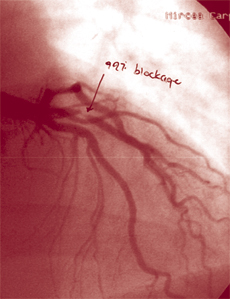

That was until Gorran experienced chest pain last fall, and an X-ray scan of his heart showed 99 percent blockage in a coronary artery that had been clear a few months before he started on the Atkins diet. Gorran underwent balloon angioplasty to clear the artery, and then on May 26, he filed suit against the Atkins company and Atkins’ estate. The Atkins diet “gave me heart disease,” he claims.

The study reflects what Gorran experienced, as alleged in his lawsuit. The Florida man’s medical records show that before going on the Atkins diet, his LDL concentration was a healthy 81 mg/dl. Shortly after changing his eating habits to favor high-protein, high-fat fare, his LDL cholesterol spiked to 138 mg/dl.